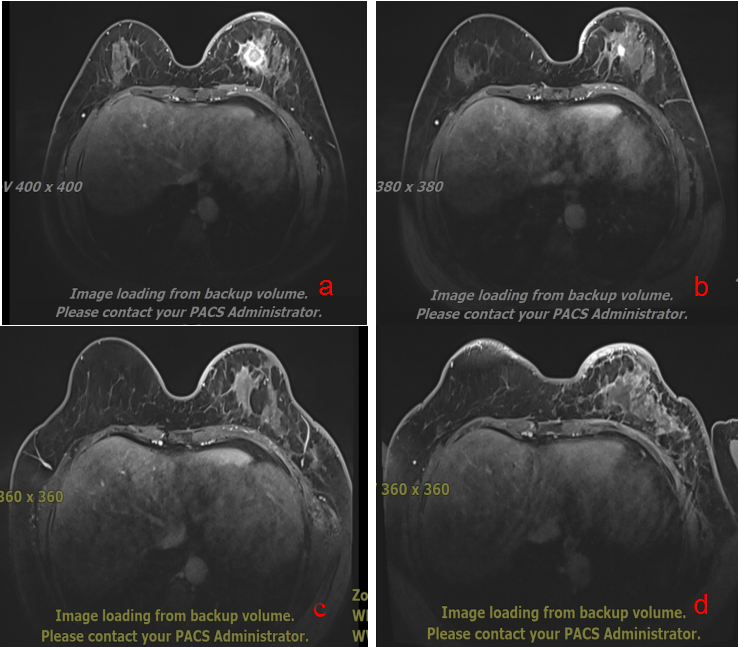

8位患者接受碳(重)离子根治性放疗,肿瘤均在3-12个月完全消失,目前所有患者均存活,局部肿瘤控制良好,3例乳腺癌患者肿瘤完全消失达CR,其中2例为三阴性乳腺癌(图4-5)

图4 43岁 左乳恶性肿瘤 T2N1M0 IIb期 a 碳离子治疗前 b碳离子治疗后 C碳离子治疗后3个月 d 碳离子治疗后6个月

图5 45岁 左乳恶性肿瘤 T4bN3M0 IIIc期 a 碳离子治疗前 b碳离子治疗后 C碳离子治疗后3个月 d 碳离子治疗后6个月